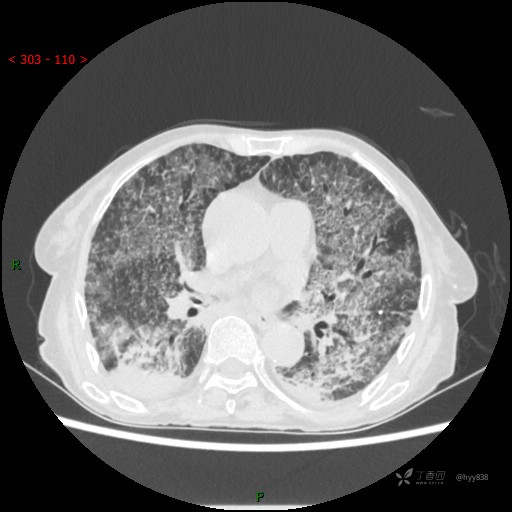

肺部弥漫性、疑难病变,感染或肿瘤?一元论或二元论?贴贴精彩---结果公布~

临床诊断:重症肺炎

胸部CT平扫